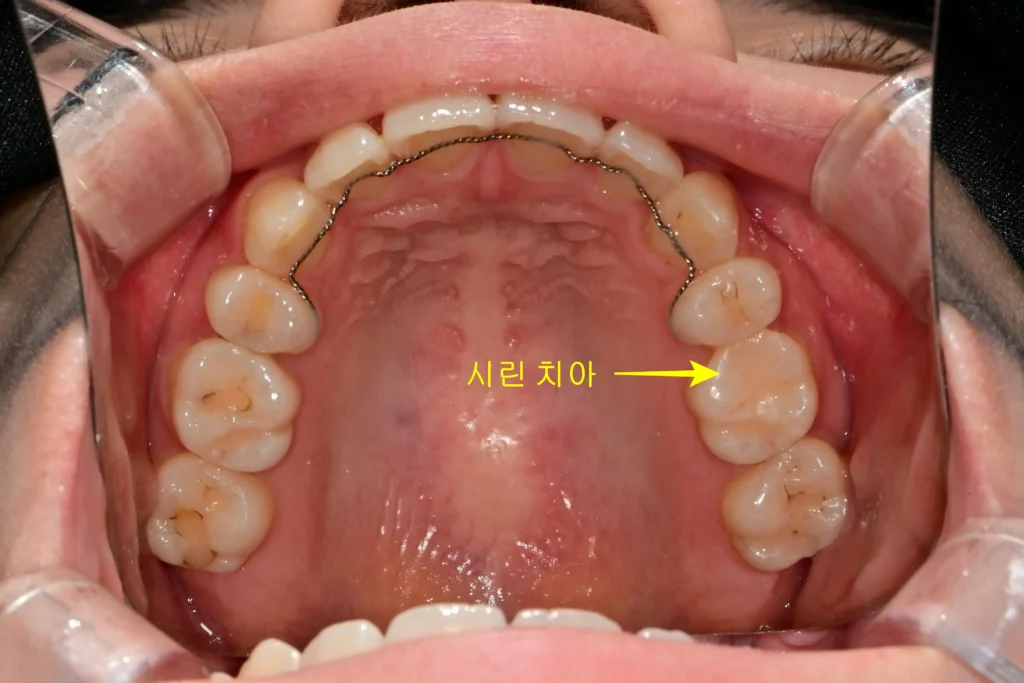

미국에서 치료받은 치아에 통증이 지속된다고 하셨습니다. 환자분은 6개월 전 미국에서 왼쪽 위 어금니 레진 치료를 받았습니다. 당시 꽤 큰 비용을 지불했다고 합니다. 하지만 치료 후 차가운 물을 마실 때마다 소스라치게 놀랄 정도의 통증을 느꼈다고 합니다.

육안으로 볼 때는 치아가 깨끗해 보였습니다. 하지만 X-ray 촬영 결과는 달랐습니다. 기존에 치료된 레진 하방으로 깊은 충치가 관찰되었습니다. 신경관과 거의 닿아 있을 정도로 아주 깊은 상태였습니다. 충치가 깊어 신경과 가까울수록 레진 치료 시 접착에 매우 신경 써야 합니다. 접착이 완벽하지 않으면 치아와 레진 사이 경계면이 계속 자극을 받습니다.